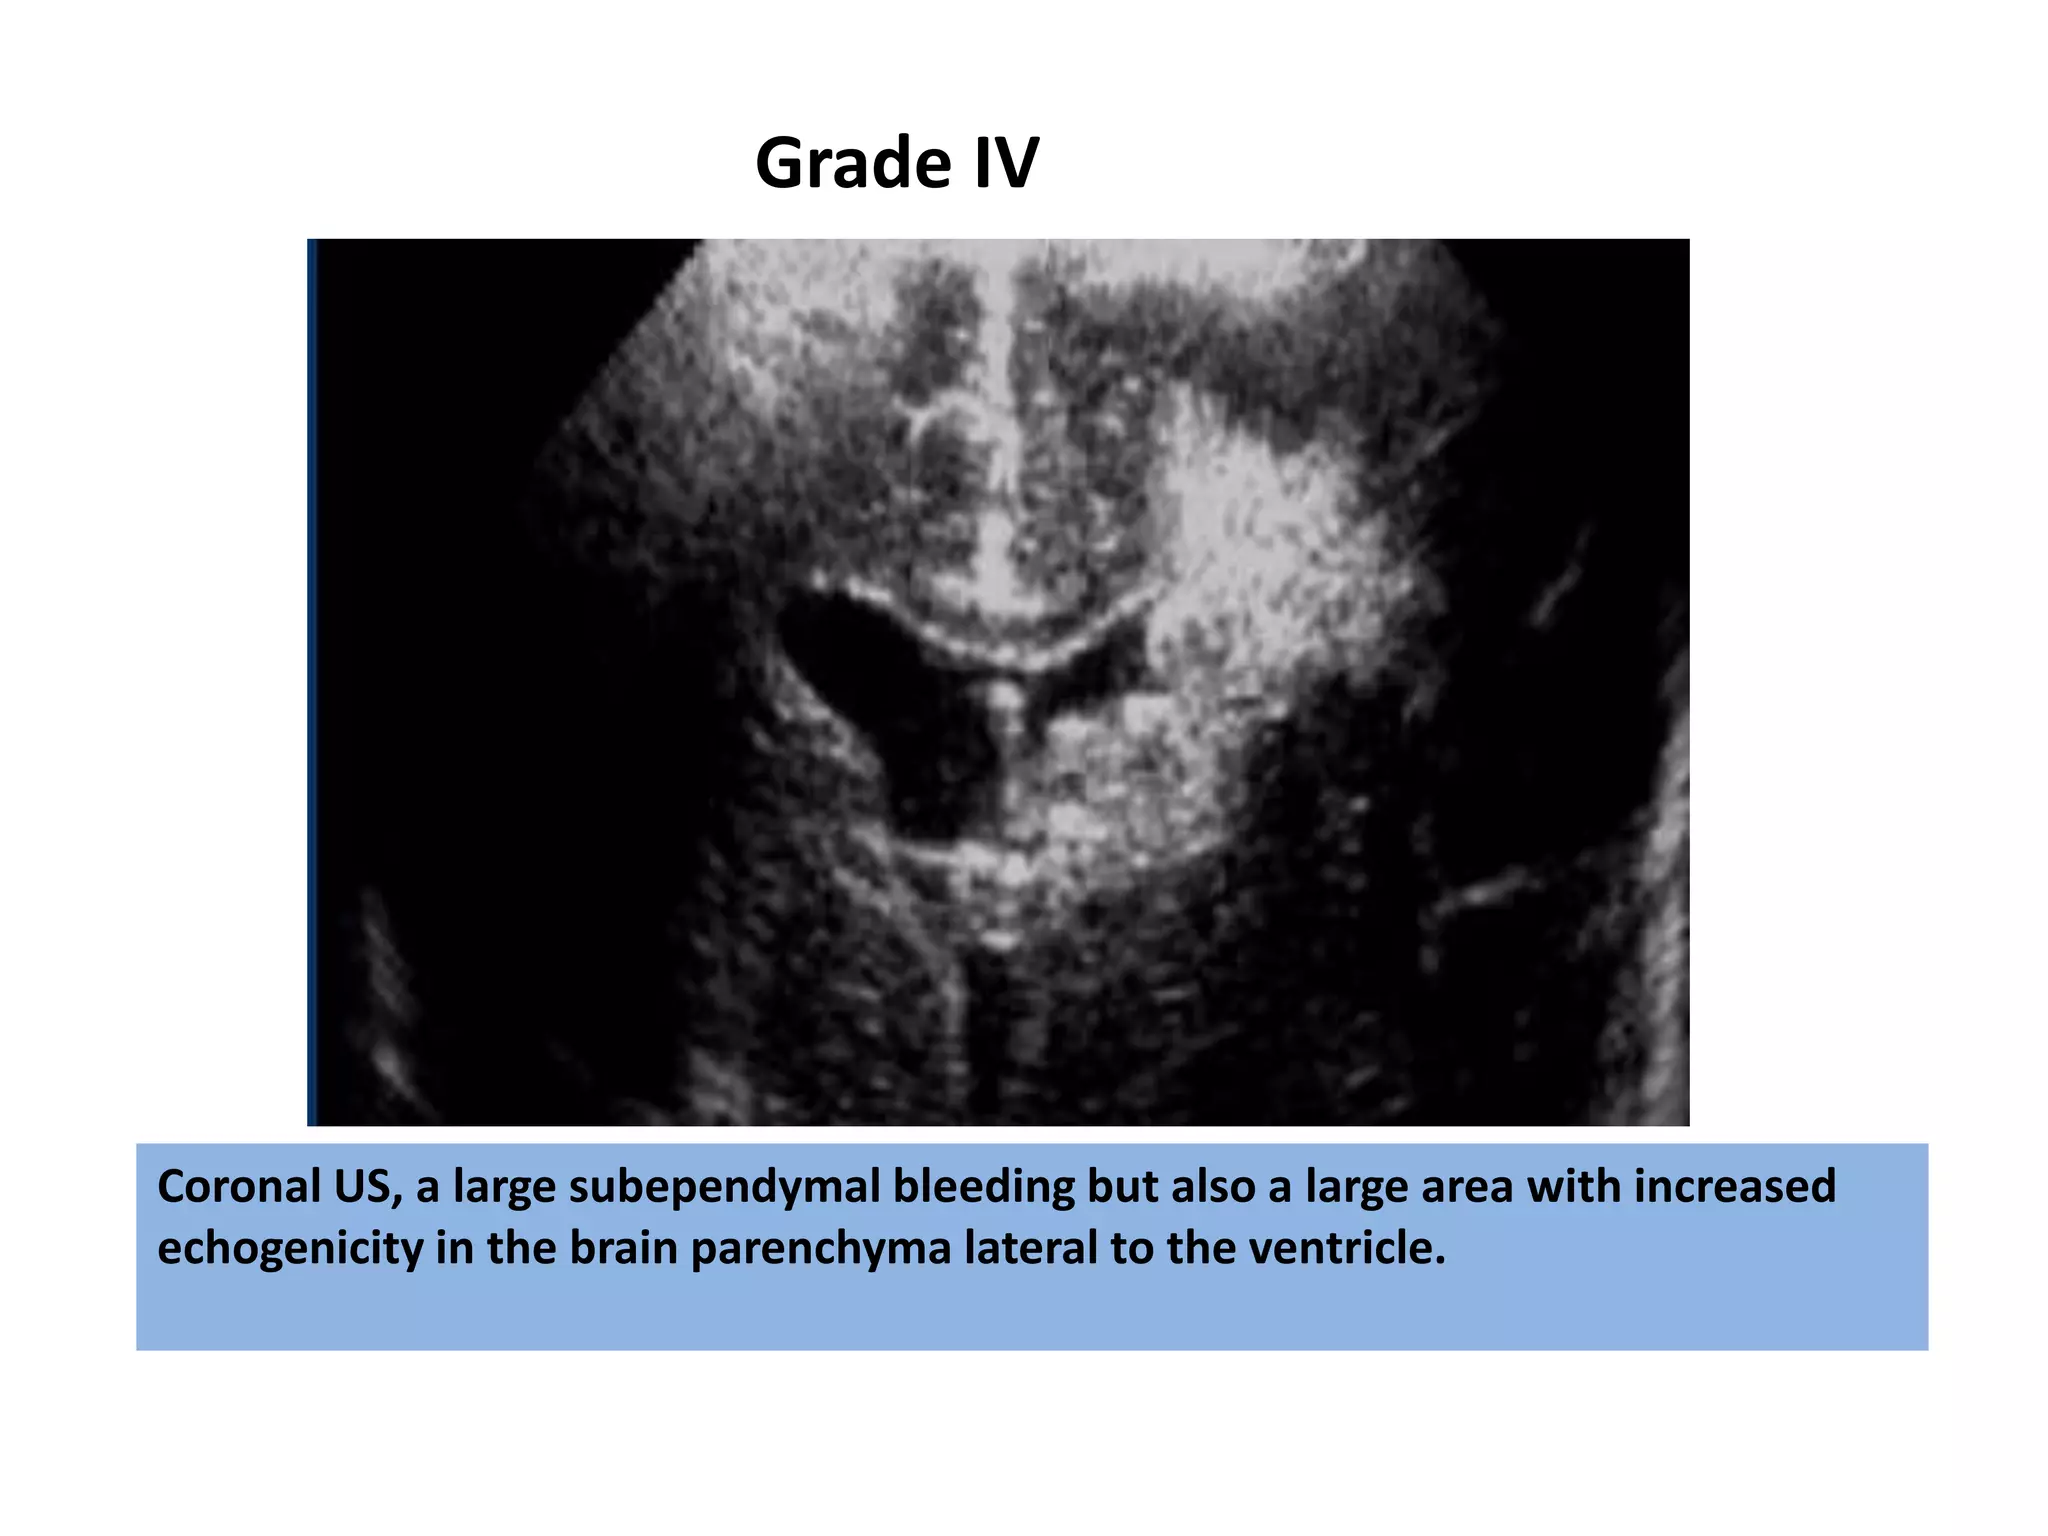

Coronal US, a large subependymal bleeding but also a large area with increased

echogenicity in the brain parenchyma lateral to the ventricle.

Grade IV

Coronal US, alarge subependymal bleeding but also a large area with increased echogenicity in the brain parenchyma lateral to the ventricle. Grade IV